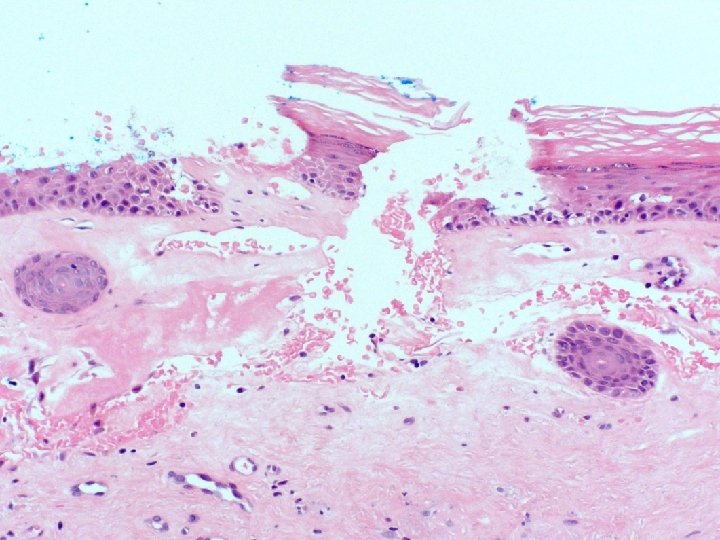

�Case number: 186 �Clinical: Male 44. Excision of irritated skin lesion behind right ear.

�Case number: 186 �Clinical: Male 44. Excision of irritated skin lesion behind right ear. �Specimen: Skin tag. �Macro: A grey polypoid fragment of skin 9 x 5 x 5 mm.

� Most popular diagnosis � Epithelioid haemangioma